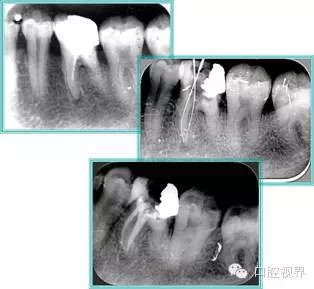

6. 鈣化

常見有修復(fù)性鈣化和增齡性鈣化。下面為根管鈣化 X 線片。

9.webp.jpg

解決方法: ( 1 )清楚根管系統(tǒng)解剖形態(tài)。 ( 2 )安全頭的金剛砂鉆開髓,低速球鉆磨除鈣化牙本( ET20 ,ET40 ,DG-16 )。 ( 3 )徹底去除髓腔周壁的牙本質(zhì)齡。 ( 4 )借助化學(xué)性藥劑,如EDTA 等。

( 5 )初銼選用 8# 或 10#K 銼,平衡力法探察到工作長度 , H銼上下提拉法使根管擴(kuò)大,提高工作效率